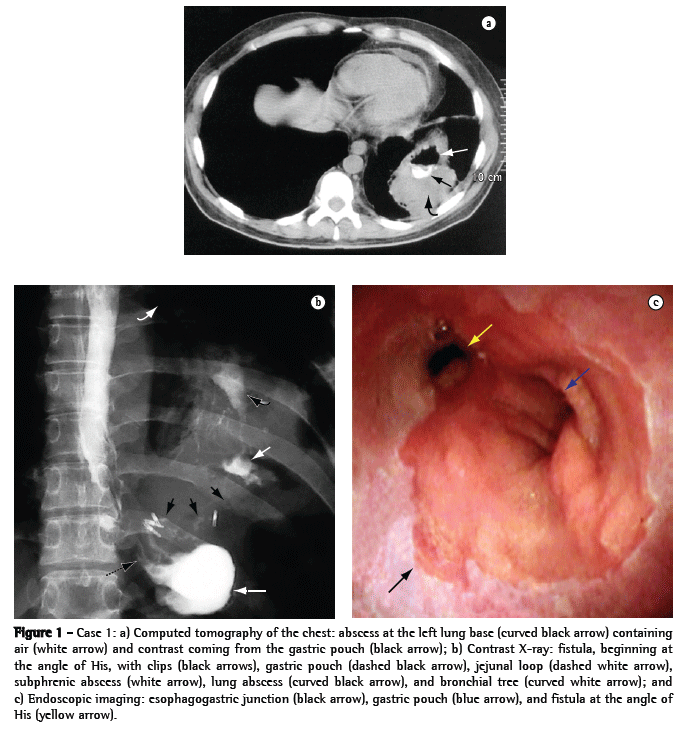

A 44-year-old female patient who underwent vertical banded gastroplasty (sleeve gastrectomy) by laparoscopy developed gastric fistula and presented five episodes of subphrenic abscess over an 8-month period. Her clinical symptoms began with pain in the left shoulder and worsened to include fever, cough, leukocytosis, worsening of overall health status, and excessive weight loss. The last two episodes were accompanied by cough with purulent expectoration, and computed tomography of the chest diagnosed an abscess at the left lung base (Figure 2a), secondary to subphrenic abscess at the angle of His, and gastric stenosis at the level of the band and the incisura angularis. The lung abscess resulting from the gastrobronchial fistula was drained through a catheter seen on a contrast X-ray (Figure 2b), and endoscopic imaging showed the internal opening of the fistula at the angle of His (Figure 2c).

The patient was monitored by a pulmonologist, an endoscopist, and a surgeon. She was treated with antibiotic therapy, respiratory therapy, and nutritional support provided through a nasogastric tube. In addition, the patient underwent exploratory laparoscopy for removal of the band, at which point a severe inflammatory obstruction was seen in the left subphrenic region and in the esophagogastric junction, making it impossible to gain surgical access to the fistula.

Therefore, we carried out six endoscopic stenostomy sessions using an electric scalpel and dilatation of the stenotic area, thereby allowing satisfactory food intake, nutritional recovery, and cicatrization of the lung abscess, after the permanent closure of the fistula.